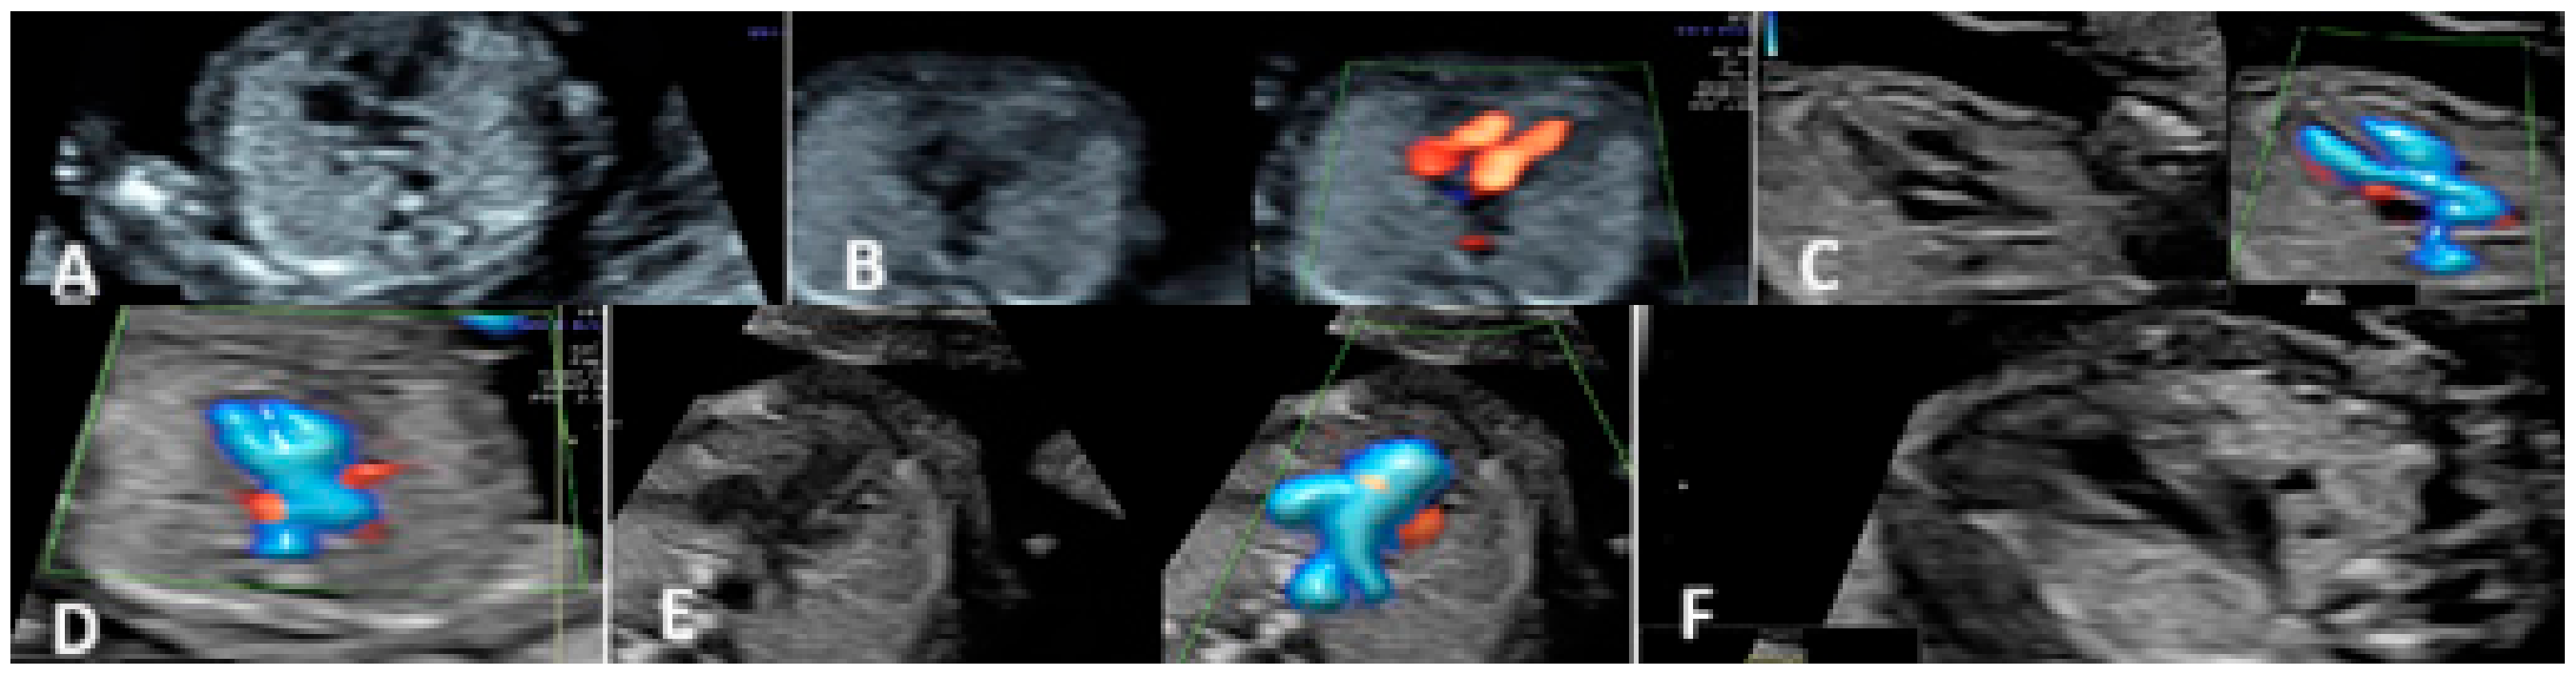

3.1. First-Trimester Evaluation

| Common arterial trunk/Tetralogy of Fallot | 9 | 9/37 (24.3%) | ||

| Hypoplasia of the left heart/coarctation of the aorta | 7 | 7/37 (18.9%) | ||

| Right aortic arch | 5 | 1 | 5/37 (13.5%) | 1/17 (5.88%) |

| Atrio-ventricular septal defects | 4 | 4/37 (10.81%) | ||

| Double outlet right ventricle | 3 | 3/37 (8.11%) | ||

| D-transposition of the great arteries | 3 | 3/37 (8.11%) | ||

| Univentricular heart | 2 | 2/37 (5.41%) | ||

| Complex cardiac malformation | 2 | 2/37 (5.41%) | ||

| Tricuspid valve atresia with VSD | 1 | 1/37 (2.7%) | ||

| Major interventricular septal defect (VSD) | 1 | 1/37 (2.7%) | ||